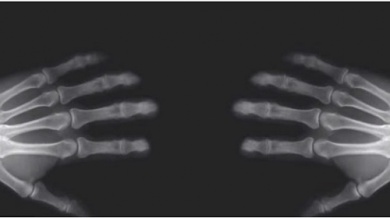

As articulações são o ponto em que os ossos se encontram e se unem.

Todas as articulações têm uma área chamada cápsula articular, que é a que as protege.

Além disso, contém um lubrificante natural chamado líquido sinovial; que é necessário para o movimento da articulação.

É exatamente este líquido que influencia o famoso “estalo”.

Visto que dentro dele há ar, e ao estalar os dedos, a articulação se separa e amplia o espaço dentro da cápsula articular.

Provocando, por outro lado, que os gases dissolvidos formem bolhas para ocupar o novo espaço criado. Ao aplicar a força nas juntas, as bolhas formadas escapam rapidamente.

É assim que ocorre o som característico dos estalos.